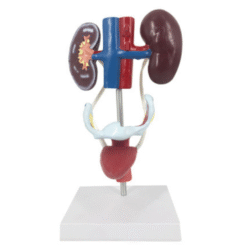

ATL-12 MALE MUSCLES FIGURE 2 PARTS

The model is an anatomically accurate representation of the human anatomy, complete with superficial and deep musculature, the digestive system, lymphatic system, respiratory system, urinary system, circulatory system, endocrine system, and nervous system. Our model has removable organs and dissectible features for a complete educational experience.

Classification:

Skeleton Models(human bone, muscle, etc.)